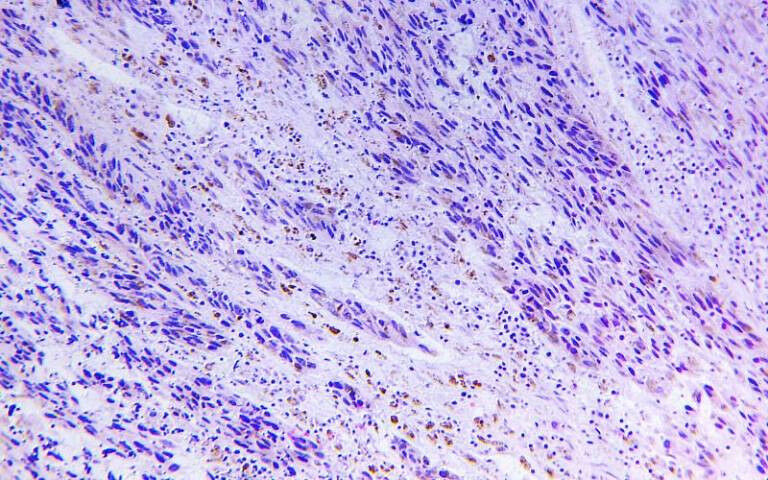

Melanoma close-up A study, co-led by researchers at UCL, has revealed how some skin cancers stop responding to treatment at the end of life. The discovery, scientists say, provides vital clues for developing new treatments for those with a terminal diagnosis. An in-depth analysis of 14 patients who died from incurable melanoma has revealed that changes to the order, structure and number of copies of tumour DNA could cause some skin cancers to resist treatment. These changes also explain how melanoma can spread to other parts of the body. The research, published in the journal Cancer Discovery, was led by scientists and clinicians at the UCL Cancer Institute, the Francis Crick Institute and The Royal Marsden. It is part of the Cancer Research UK-funded PEACE study, which is shedding light on the final stages of life with cancer by analysing tumour samples taken from autopsies with informed consent. Dr Mariam Jamal-Hanjani, Clinical Associate Professor at UCL Cancer Institute and lead investigator of the PEACE study, said: "These results present the most detailed picture yet of what melanoma looks like at the final stages of life.